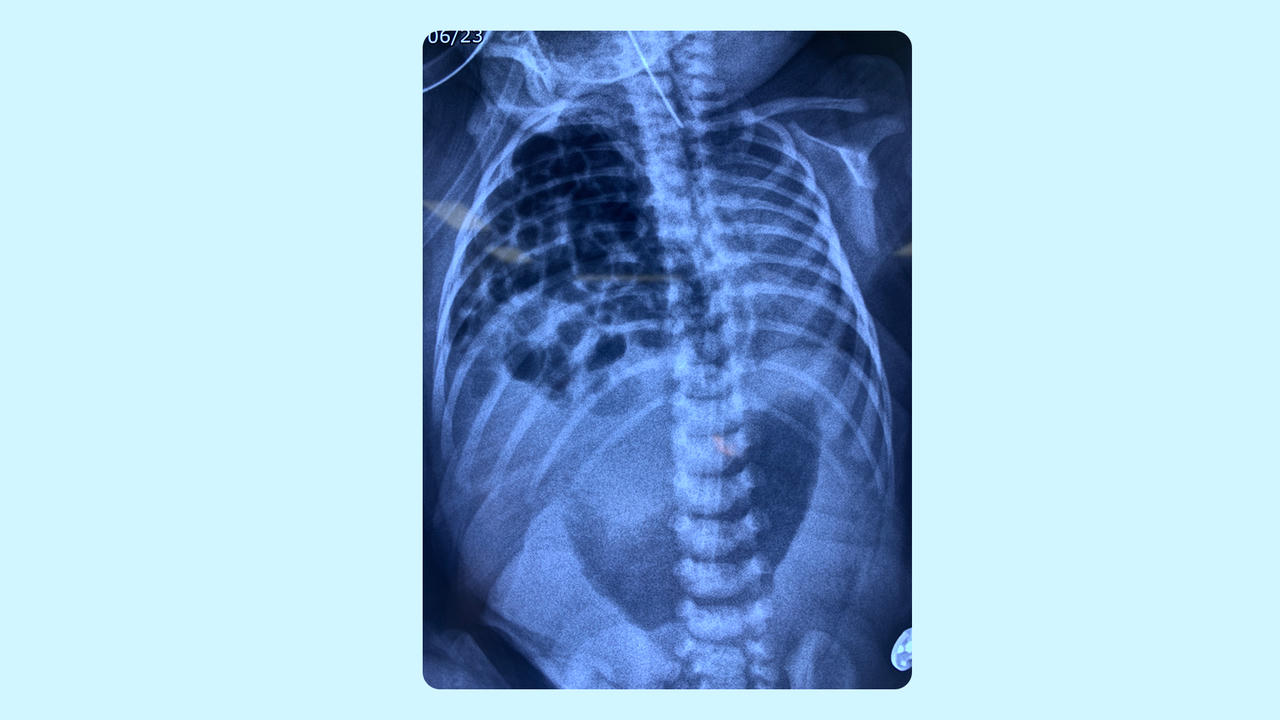

Hình ảnh siêu âm cho thấy toàn bộ ruột và một phần gan thoát ra ngoài cơ hoành bé gái. Ảnh: Hạ Vũ |

ThS.BSNTCKI Trần Lâm Khoa, bác sĩ chuyên phụ trách thai kỳ nguy cơ cao Trung tâm Sản Phụ khoa BVĐK Tâm Anh cho biết, bé Thanh An (7 ngày tuổi, TP HCM) được phát hiện dị tật thoát vị hoành ở tuần thứ 21 của thai kỳ. Khi đó, một phần gan, túi mật, ruột non và ruột già của bé chui lên lồng ngực bên phải, khiến phổi bị phải thiểu sản nghiêm trọng.

Cơ hoành là một hàng rào cơ hình vòm nằm giữa khoang ngực và khoang bụng; ngăn cách tim, phổi với các cơ quan trong ổ bụng (dạ dày, ruột, lá lách, gan). Tỷ lệ thoát vị hoành bẩm sinh ở trẻ khoảng 3/10.000 trường hợp. Trong đó, thoát vị hoành phải khoảng 20% trường hợp; khiến gan, ruột di chuyển lên ngực thông qua một lỗ hổng (khe hở) ở cơ hoành và chèn ép phổi phải.